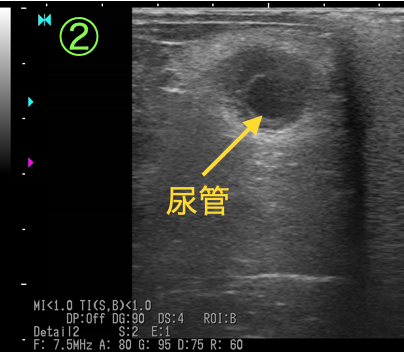

断面③④

腫瘤①に巻き込まれた尿管は、断面②と比較すると押しつぶされるようにして狭窄しています。

以上の画像と触診から、腫瘤①が尿管を巻き込むように形成されており、巻き込まれた尿管は著しく狭窄し(③④)、腎盂および腫瘤より腎臓側の尿管は鬱滞した尿により著しく拡張している(①②)ことがわかりました。